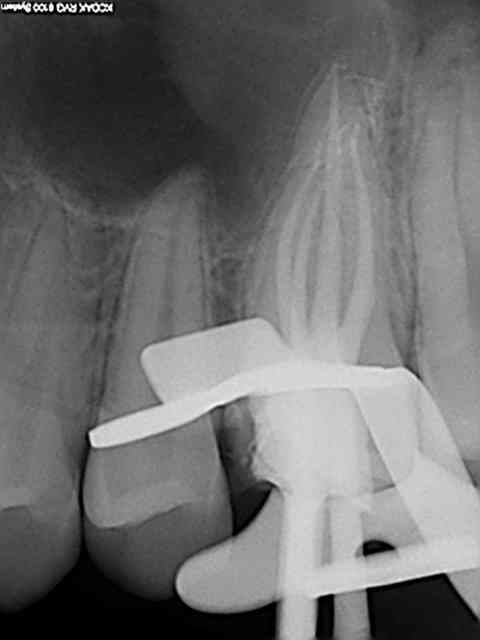

Tiens les endos de la semaine, que d'apex défoncés !-))

La 47 en fin le distal est obturé au système B (bouchon apical) et au mac spaden pour la partie coronaire, tu vois la différence à la radio ? Alors l'apex défoncé il faut avoir l'oeil ! peut etre mais à 25 centièmes et à conicité 6 %........-))